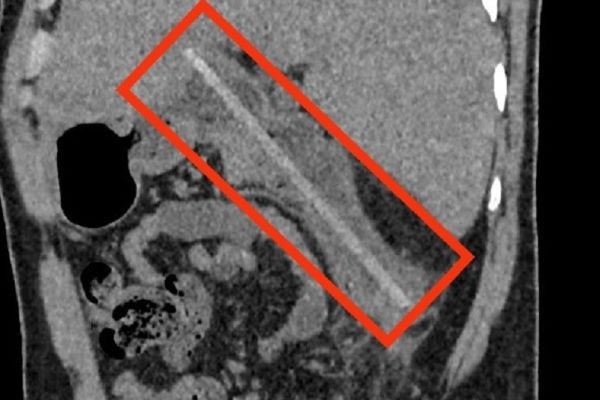

飲み会の一発芸で箸を飲み込んだ男性、3か月後に緊急手術 [三面]

飲み会の一発芸で箸を飲み込んだ男性、3か月後に緊急手術[三面]

ホーチミン市クチ郡のスエンアー総合病院は6日、消化管穿孔で緊急搬送された男性の手術を行ったと発表した。男性は3か月前の飲み会の席で、箸を...